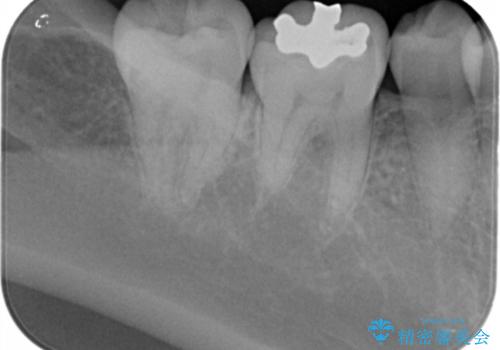

- 口を開けたとき銀歯が見えるのが嫌で白くしたいとの事で来院。

銀歯を除去してセラミックインレー(e-maxインレー)での治療となりました。